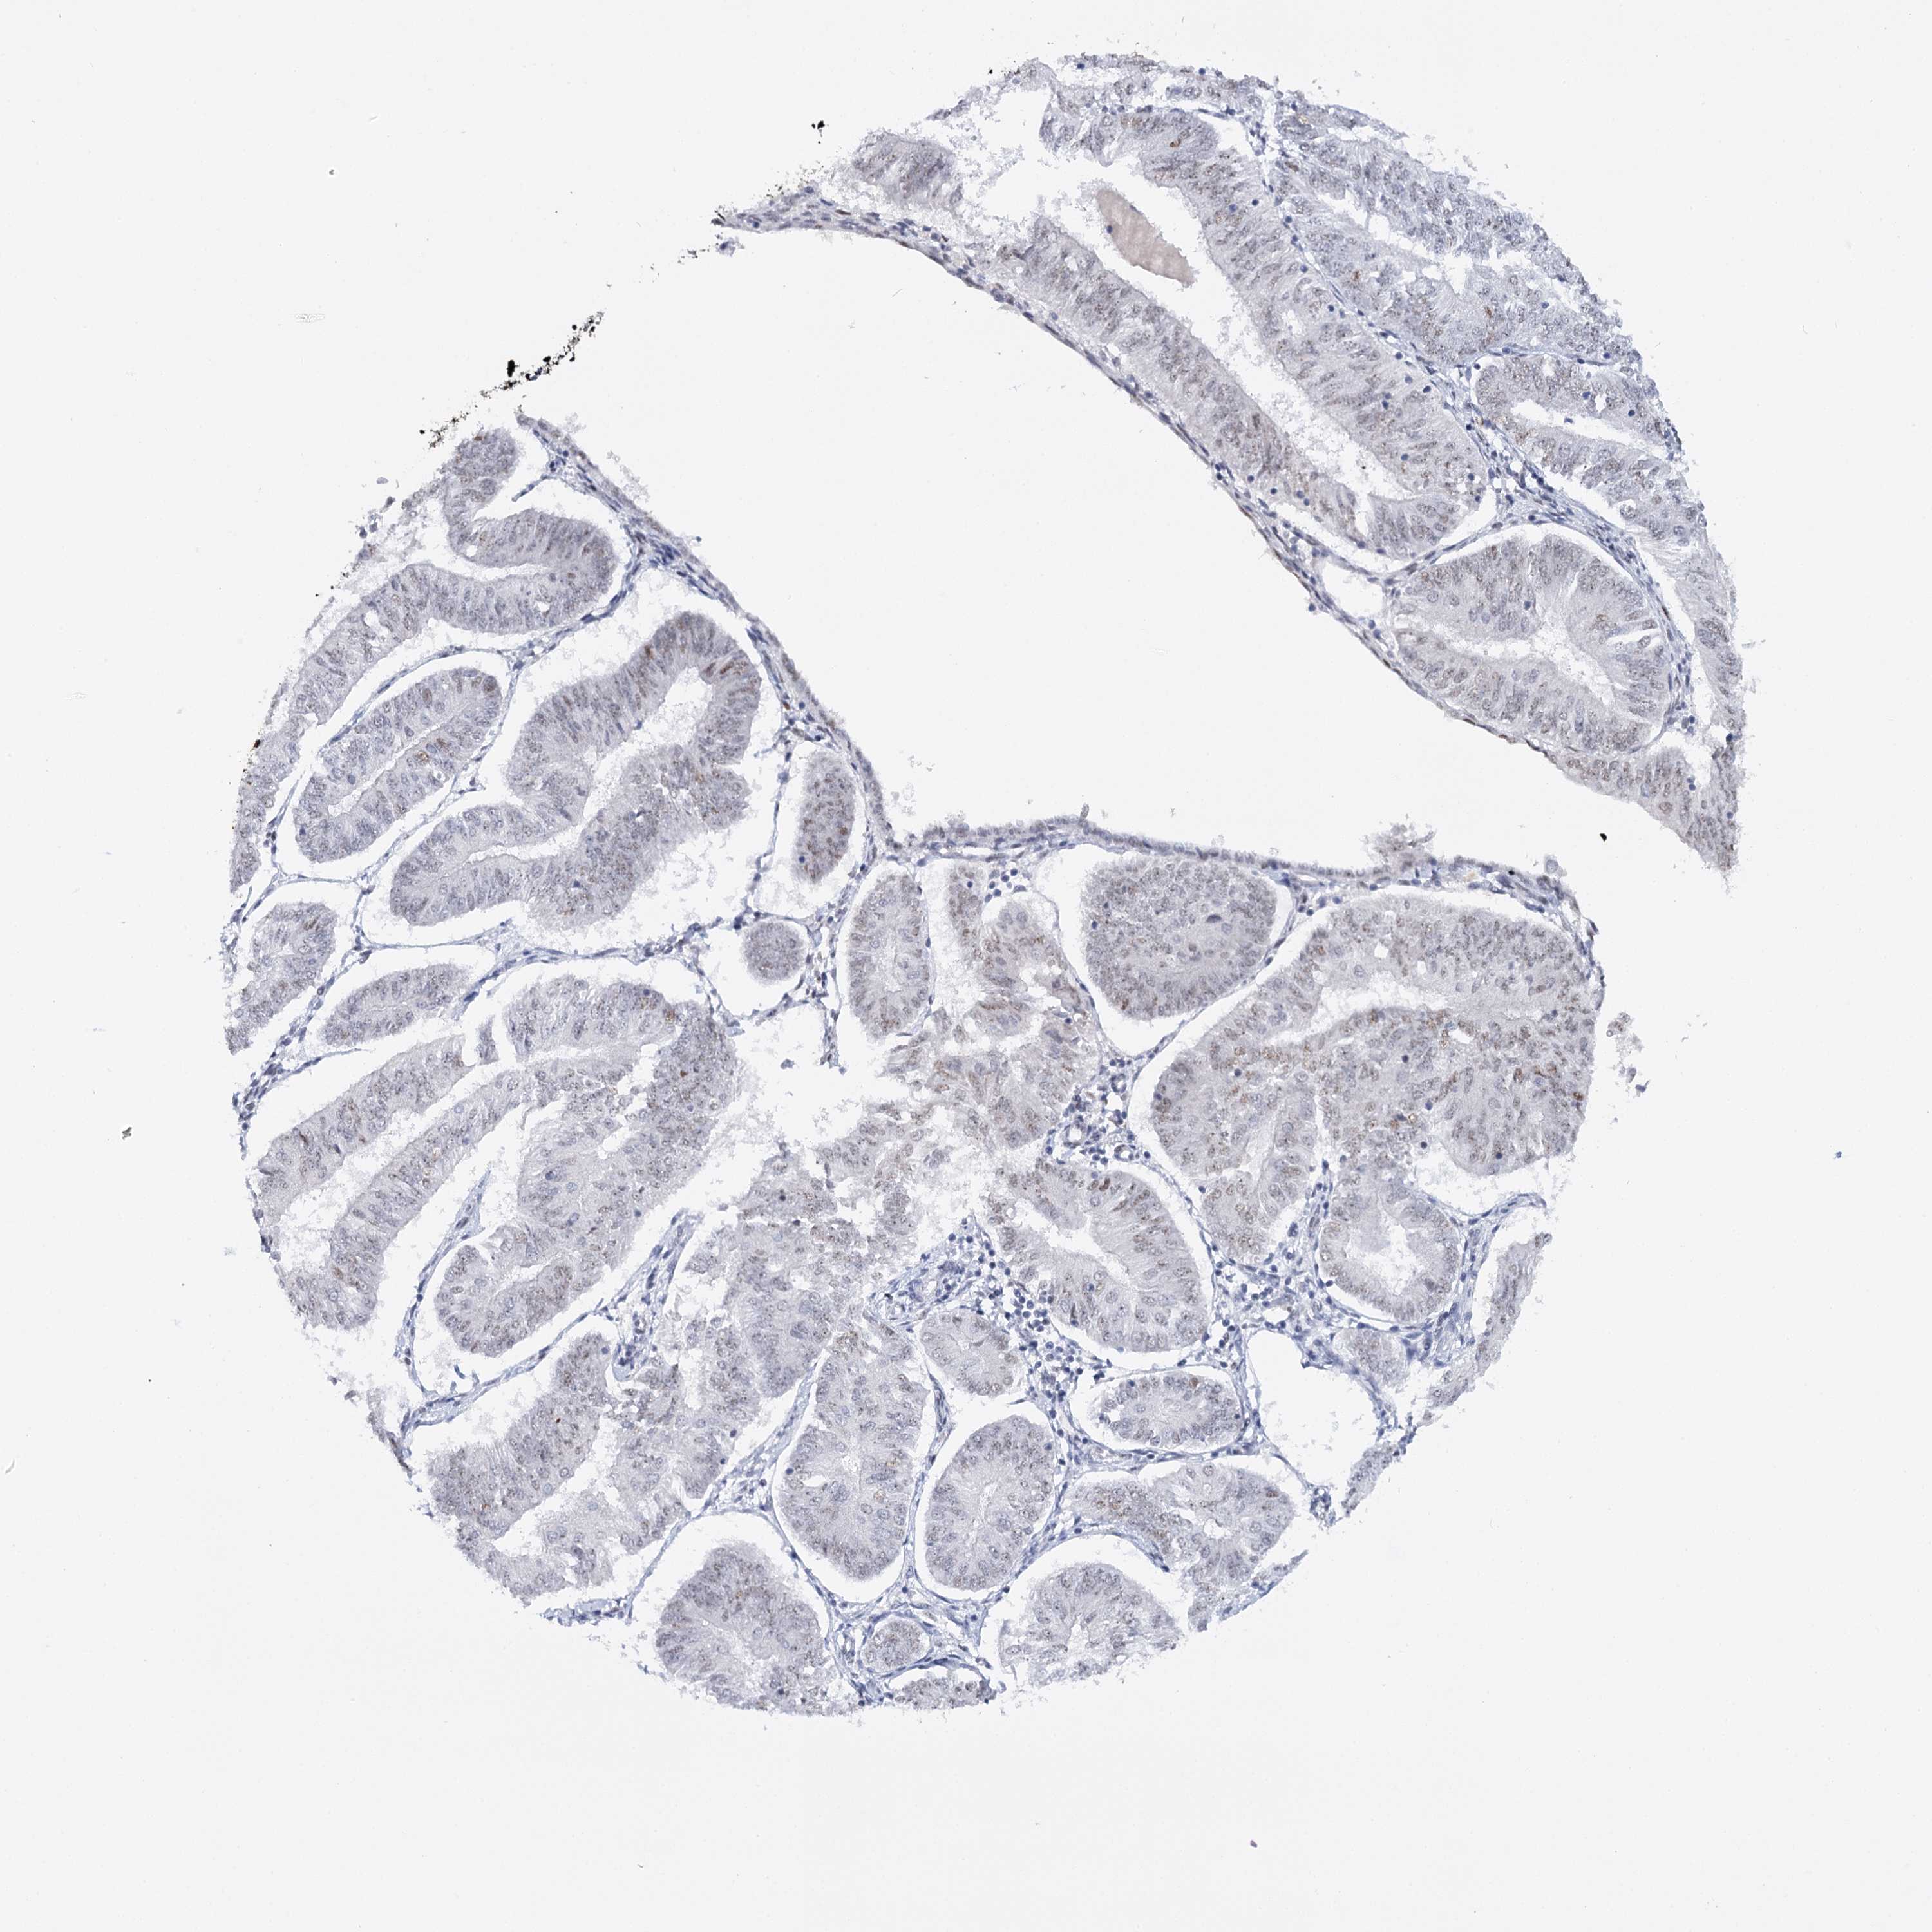

ENDOMETRIAL CANCER - Protein expressioni

A mouse-over function shows sample information and annotation data. Click on an image to view it in a full screen mode. Samples can be filtered based on level of antibody staining by selecting one or several of the following categories: high, medium, low and not detected. The assay and annotation is described here.

Note that samples used for immunohistochemistry by the Human Protein Atlas do not correspond to samples in the TCGA dataset.

Antibody stainingi

Antibody staining in the annotated cell types in the current human tissue is reported as not detected, low, medium, or high, based on conventional immunohistochemistry profiling in selected tissues. This score is based on the combination of the staining intensity and fraction of stained cells.

Each image is clickable and will lead to virtual microscopy that enables deeper exploration of all samples and also displays staining intensity scores, fraction scores and subcellular localization as well as patient and tissue information for each sample.

Antibody CAB002973

Antibody CAB039238

Antibody CAB039239

Antibody CAB072876

Staining

High

Medium

Low

Not detected

Intensity

Strong

Moderate

Weak

Negative

Quantity

>75%

75%-25%

<25%

None

Location

Nuclear

Cytoplasmic/membranous

Cytoplasmic/membranous,nuclear

Adenocarcinoma, NOS

Neoplasm, malignant, NOS

Adenocarcinoma, metastatic, NOS